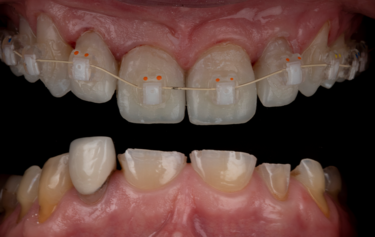

Figure 7: Indirect orthodontic bracket bond-up stents in-situ

Figure 8: Immediate result after stent-guided composite build-up and orthodontic bracket placement

The full restoration of all the patient’s upper and lower teeth was completed using this process at the same visit in only 2 hours. We were able to immediately then place upper and lower orthodontic brackets using an in-direct set-up technique through CFast orthodontics. This stent-guided application method means a much quicker and simpler fixation of the bracket to the teeth. Due to the incredible accuracy of the SmileFast stent, the composite restorations placed are a perfect replication of the digital model on which the orthodontic set-up was manufactured, therefore the stent for the orthodontics was a perfect fit, as shown in Figure 7. Within 4 hours all the patient’s teeth were fully restored and the fixed orthodontics applied and activated with 0.014 NiTi wires (Fig. 8). After 5-months the teeth were aligned into a more favourable position and the passive over-eruption of the teeth had been reversed (Fig.9). The patient was comfortable and occlusion functioning well, so it was decided to move forward with the second phase of her rehabilitation, the planning and provision of her final ceramics.